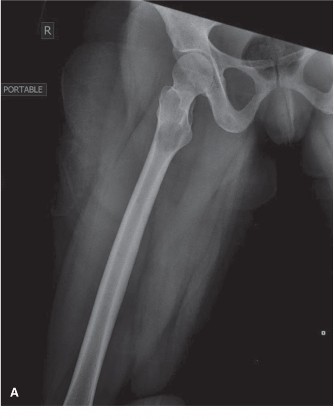

* Location: While classically described as a diaphyseal tumor of long bones, ES can occur in any bone or even in soft tissues.

* Appendicular skeleton: Approximately 40-50% of cases, commonly in the femur, tibia, humerus, and fibula.

Long Bones

- Diaphyseal Involvement: ES frequently involves the diaphysis or metadiaphysis, often leading to significant cortical destruction and soft tissue extension. The peritumoral edema and reactive zone are extensive, requiring wide margins that may necessitate resection of a substantial segment of the bone.

This image potentially depicts a radiographic representation of a Ewing sarcoma in a long bone, highlighting the typical diaphyseal involvement and periosteal reaction.